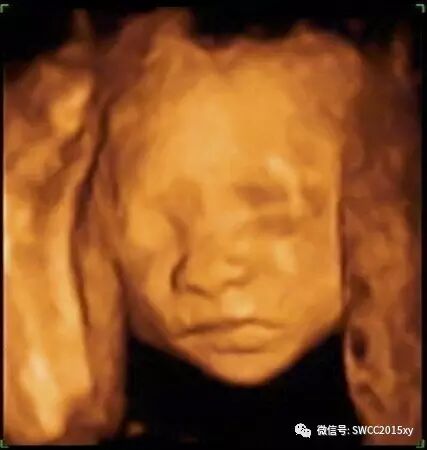

在临床中经常遇到一些孕妇说自己的下腹部疼痛,这是咋回事呢?由于怀孕后子宫变大,子宫韧带受牵扯而引起。通常这种疼痛并不会很严重,可能会造成一些不适,但不会影响日常生活。疼痛的位置并不固定,有时在左下腹,有时则在右下腹,疼痛时间持续很短。

在孕早期,有些腹痛是生理性的,即因为怀孕所引起的正常反应,但有些却是病理性的,可能预示着流产等危机的发生。 1.早孕反应性腹痛 孕早期很多准妈妈总感觉有些胃痛,有时还伴有呕吐等早孕反应,这主要是由孕早期胃酸分泌增多引起的。这时要注意饮食调养,膳食应以清淡、易消化为原则,早餐可进食一些烤馒头片或苏打饼干等。随着孕早期的结束,这种不适会自然消失。

2.病理性腹痛 在孕早期出现腹痛,特别是下腹部疼痛,首先应该想到是否是妊娠并发症。常见的并发症有先兆流产和宫外孕。 准妈妈在孕期前几个月,如果出现阵发性小腹痛或有规则腹痛,那可能预示着先兆流产。如果疼痛加剧或持续出血,需要立即就医。有些孕妈妈认为在孕早期出现腹痛可能是偶然性的,不要紧,只要躺在床上休息一下就好了。这种盲目采取卧床保胎的措施并不可取,应及时到医院检查治疗,以免延误病情。

3.生理性腹痛,在怀孕4个月左右时,子宫增大,同时子宫圆韧带被牵拉,很多准妈妈都会感觉有些腹痛。这种疼痛,部位多位于下腹部子宫一侧或双侧,呈牵涉痛、钝痛或隐痛,走较远的路或者变换体位时,疼痛会变得更明显。准妈妈不用担心,多卧床休息就可缓解。4.在孕中期行房事时过于用力,也会引起孕妈妈腹痛。